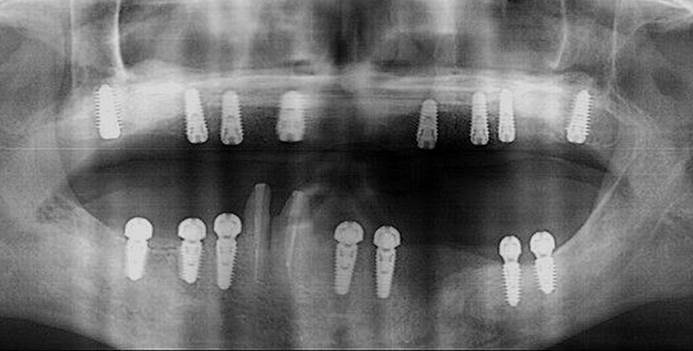

Clinical case: Full-mouth implants for mandibular & maxilla - restored using mixed prostheses

- Courtesy of Dr. Hyun Jun Kim, Korea -

Keywords

AnyRidge, full-mouth implants, mandibular, maxilla, edentulous, full mouth rehabilitation, Octa abutment, long-term clinical case, biological stability, Dr. Hyung Jun Kim